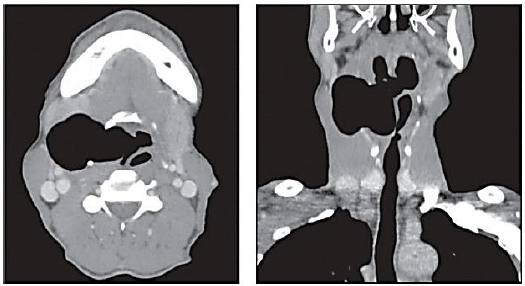

Homem, 60 anos, com história de massa cervical indolor de crescimento progressivo há nove meses, acompanhada de rouquidão. Nega dispneia; disfagia; perda ponderal; febre; ou, outros sintomas. Exame ultrassonográfico teve como laudo massa com superfície de reflexão intensa, de difícil caracterização, sugestiva de presença de gás em seu interior. Realizada aspiração por agulha fina da lesão, cujo laudo descrevia apenas material insatisfatório. Posteriormente, foi submetido à tomografia computadorizada, cujas imagens, em cortes axial e coronal, respectivamente, estão representadas a seguir:

Considerando a situação hipotética, o diagnóstico mais provável é: